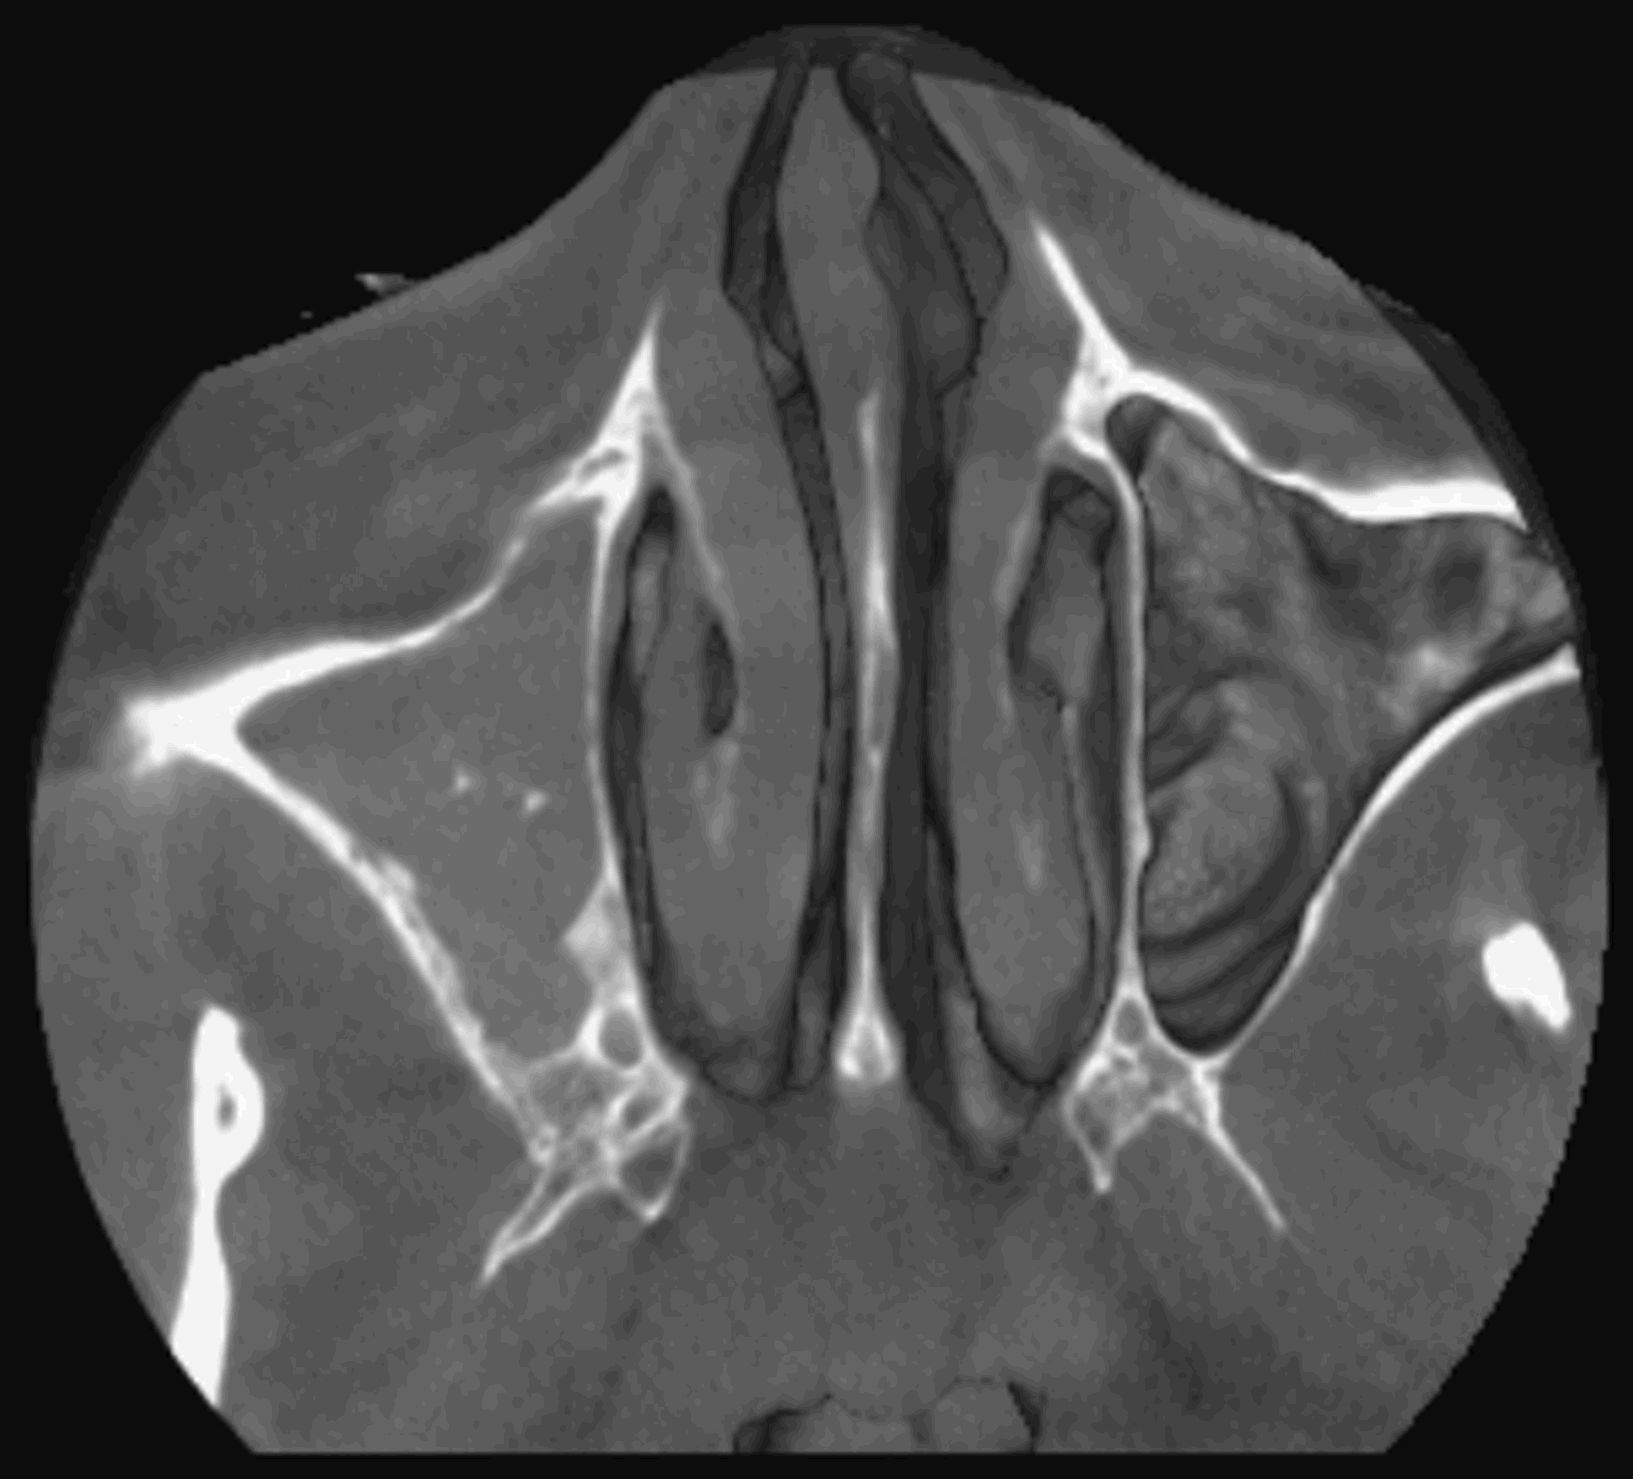

Le cone beam utilisé en pathologie dentaire et maxillo-faciale est indiqué pour l’examen des tissus minéralisés (dents, cartilages, os), il permet d’identifier les lésions osseuses, les fractures, les infections, les kystes ou les corps étrangers.

- pathologie des sinus maxillaires

Les nouvelles générations de scanner permettent de faire une acquisition d’un volume global d’une partie du corps et de travailler à l’intérieur de ce volume en isolant une structure anatomique donnée et de l’explorer dans tous les plans de l’espace.